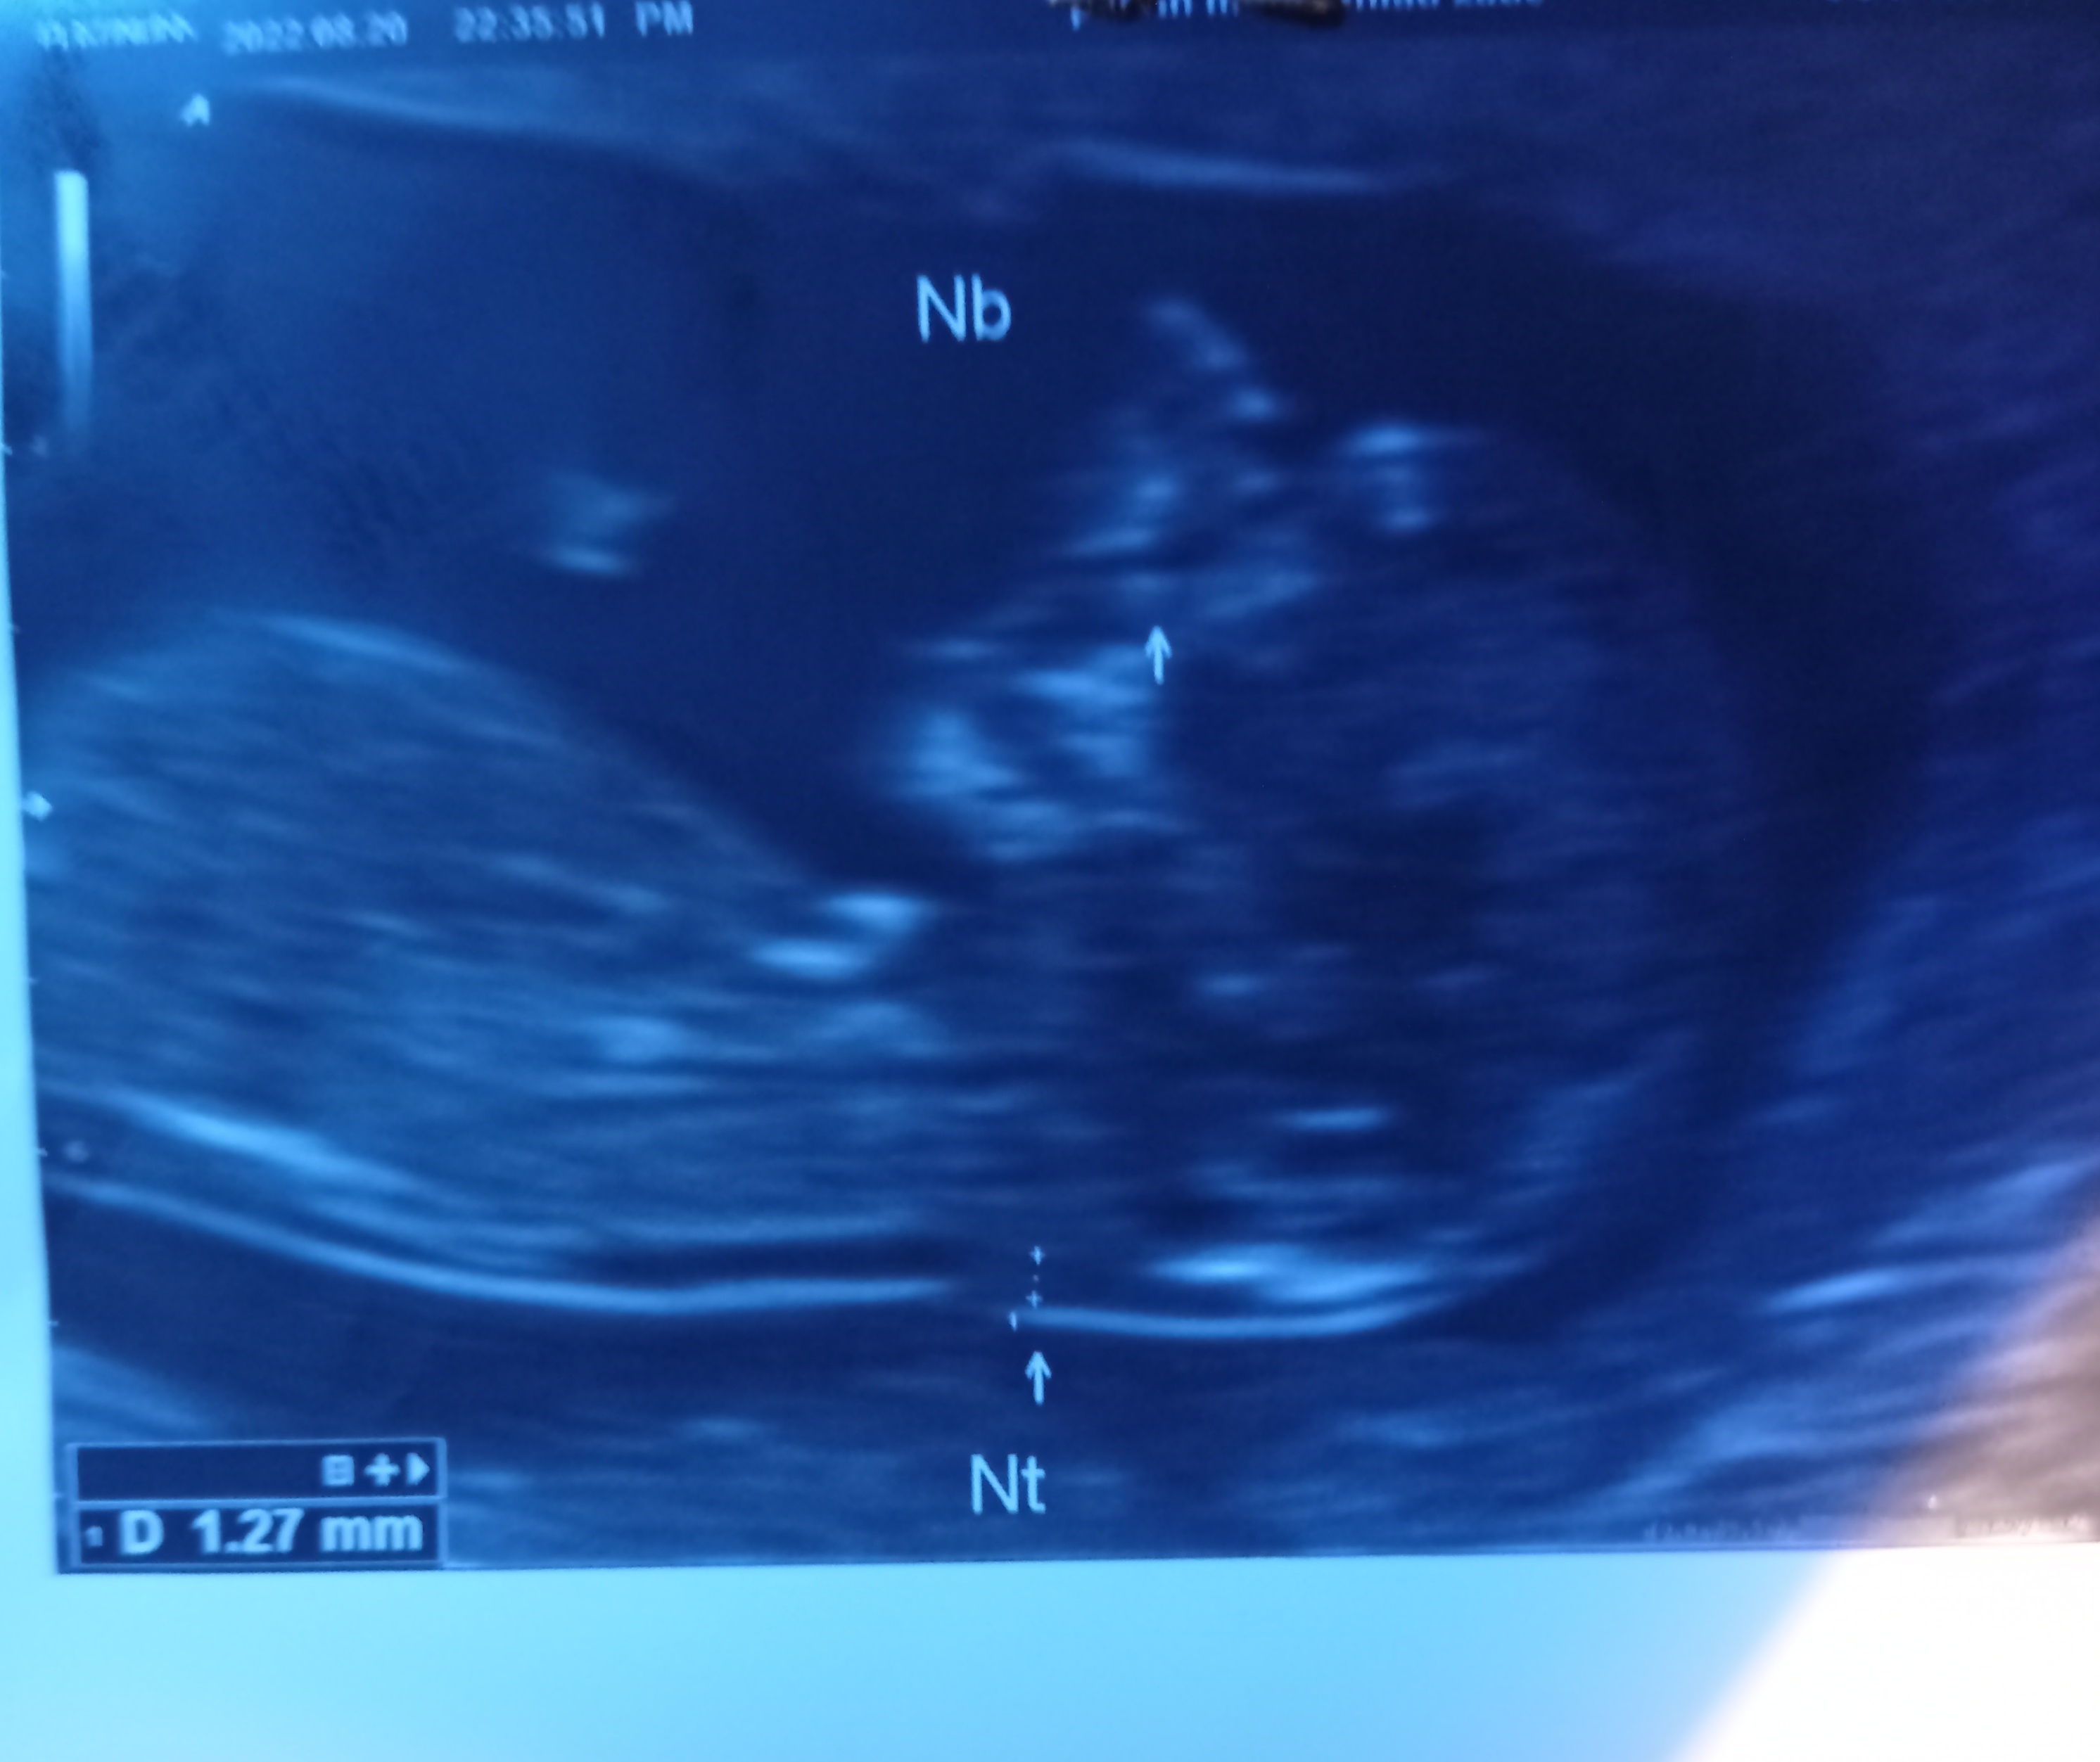

alisan72 مدیر استارتر عضویت: 1400/11/27 تعداد پست: 332 عنوان تشخیص جنسیت 102 بازدید | 11 پست سلام عکس سونو وآزمایش رو میذارم غربالگری اول .هرکی بلده جنسیت رو تشخیص بده ممنون 1401/06/01 | 14:30 0 نفر لایک کرده اند ... گزارش تاپیک نامناسب